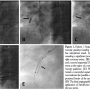

Patient 2. A 63-year-old, male smoker with a known history of diabetes, hypertension, and hyperlipidemia was admitted to our center for primary PCI due to an inferior ST-elevation MI. Initial CAG showed proximal total occlusion of the right coronary artery (Figure 2A). After crossing the lesion with a soft BMW guidewire, diffuse atheromatosis was revealed up to the distal part of the vessel (Figure 2B). After predilation with a regular 2.5 x 15 mm balloon, a long 3 x 24 mm DES was implanted and a second 3 x 14 mm DES adjacent-sequential to the first was deemed necessary by the operator following angiography. In order to implant the sequential stent optimally, StentBoost was performed just before inflation of the balloon (Figure 2C). Following deployment of the latter, a repeat StentBoost indicated sufficient stent expansion and optimal overlap between the two stents (Figure 2D; arrow). The result of PCI as deemed by final angiography was successful (Figure 2E).